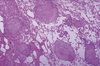

Brain HIV Encephalopathy

Aetiology of brain HIV encephalopathy

-

Diagnostic criteria for brain HIV encephalopathy

-

Outcomes of brain HIV encephalopathy

-

Brain HIV Encephalopathy High Magnification